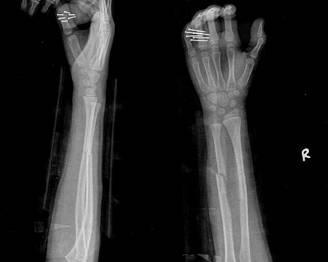

摘要:最新尺橈骨融合方法展現(xiàn)骨頭間的奇妙和諧與友情力量。通過先進(jìn)的醫(yī)療技術(shù),尺骨和橈骨之間的融合得到顯著改善。這種方法不僅提高了治療效果,還展現(xiàn)了人體骨骼之間的和諧關(guān)系。憑借友情和信念的力量,醫(yī)學(xué)界不斷突破,為患者帶來福音。

經(jīng)過醫(yī)生的診斷,小明被確診為尺橈骨融合,這是一種骨骼疾病,會導(dǎo)致尺骨和橈骨無法正?;顒樱牭竭@個消息后,小明和他的朋友們都感到有些緊張和害怕,但他們并沒有放棄,而是選擇相互鼓勵,共同面對這個挑戰(zhàn)。

在醫(yī)生的介紹下,他們了解到了一種最新的尺橈骨融合治療方法——通過微創(chuàng)手術(shù)進(jìn)行骨骼融合的新技術(shù),這種方法不僅減少了手術(shù)風(fēng)險,還能更快地恢復(fù)活動能力,雖然小明感到害怕,但他的朋友們一直陪伴在他身邊,給予他勇氣和力量。